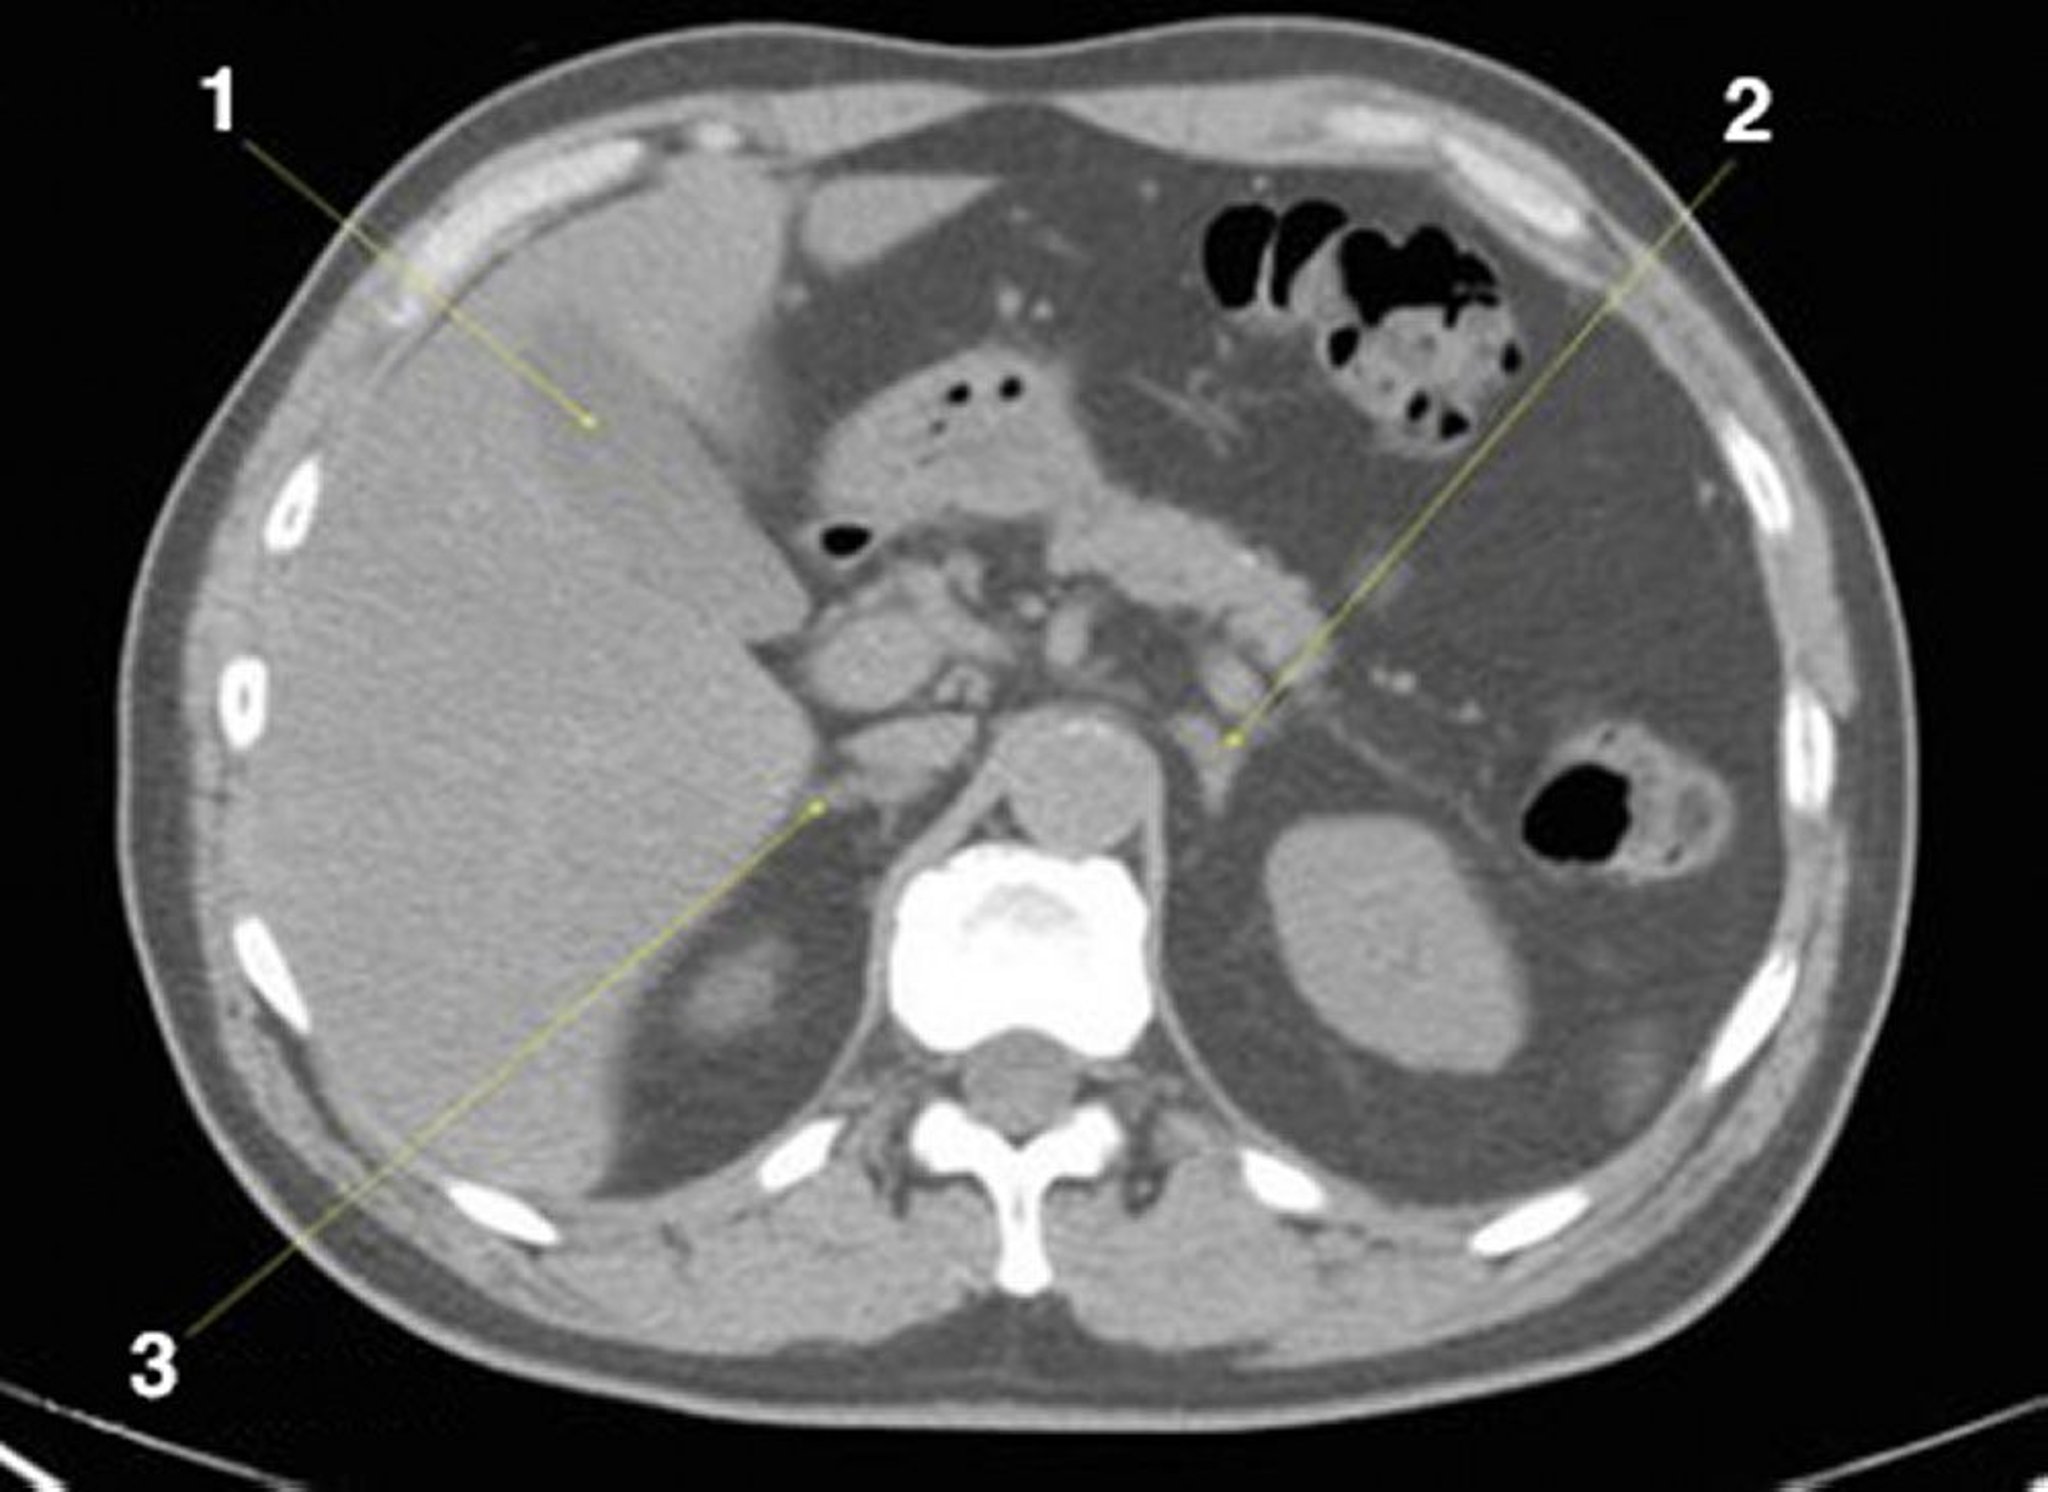

TC senza contrasto dell'addome e della pelvi che mostra l'anatomia normale (Slide 8)

1 = colecisti; 2 = ghiandola surrenale sinistra; 3 = ghiandola surrenale destra.